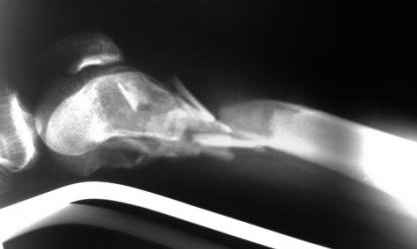

Рентгенограммы.

На рентгенограммах перелом не "н/3" бедра, что подразумевает диафиз, а перелом дистального суставного конца - крупные фрагменты мыщелков, метафиз фрагментирован, т.е. по классификации OTA/AO это 33C2.

Право слово, классификация переломов существует не зря, она помогает и выбрать вариант остеосинтеза, и даже в отсутствие рентгенограмм можно более точно обозначить проблему.

Наиболее широко распространенный подход в такой ситуации - после репозиции мыщелков использовать пластину с угловой стабильностью.

Можно и ретроградное штифтование, если есть соответствующий гвоздь.

При любом варианте фиксации надо избежать соблазна залезать открыто в метадиафизарную часть повреждения.

Мы бы начали с закрытой репозициии мыщелков под экраном, манипулируя джойстиками. Если не получается - миниартротомия. Сопоставленные мыщелки прошили бы спицами (резервируя место для гвоздя). Наложили бы спицевой дистрактор. И сделали бы антеградное штифтование гвоздем с

несколькими очень дистально расположенными отверстиями.

Остеосинтез при 33-С2 подразумевает относительную стабильность. Следовательно, показано использование мостовидного остеосинтеза пластиной с угловой стабильностью или интрамедуллярный остеосинтез без рассверливания с блокированием. Поскольку перелом открытый, то предпочтительнее выглядит второй вариант. Бедренный штифт Т2 производства Stryker при ретроградном введении даёт возможность межфрагментарной компрессии за счёт использования мыщелкового винта.

По прямой проекции складывается впечатление, что метаэпифизарная часть бедра расколота вдоль и латеральный мыщелок смещен книзу. Интрамедуллярный штифт "повиснет" между мышелками и есть вероятность, что при раннем начале движений мыщелки "разойдутся". Учитывая, что рана зажила первичным натяжением, предпочел бы пластину с костной пластикой. запасной вариант - аппарат Илизарова.